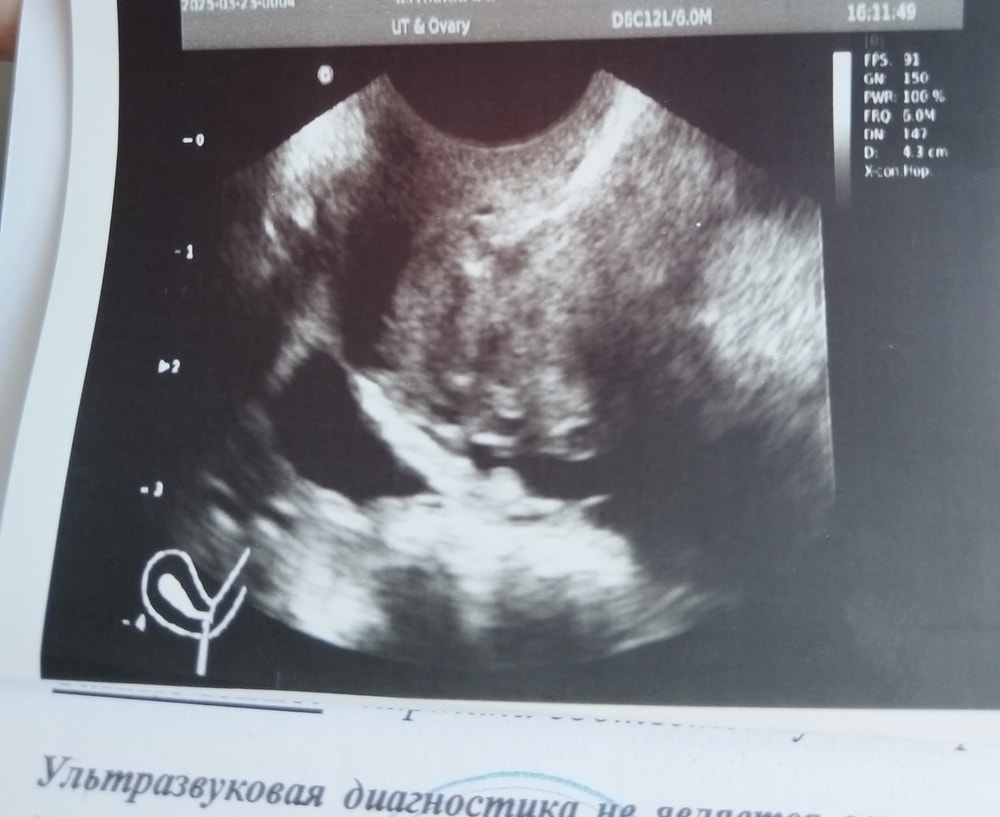

Маруся Марусина, вот еще пару снимков Изображение Изображение

Раз овуляции не было - значит ДФ. Ну и по форме на ЖТ не очень похоже

Галчонок, узист оч странный мужчина. Описание дф даже нет. Просто образование в левом и все. В позадиматочном пространстве незначительная жидкость тоже не понятно , обычно ж после овуляции появляется. Сказал ну вот только наверное начинается овуляция.